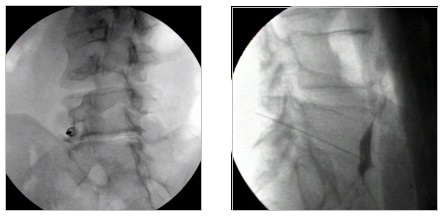

Η εμφύτευση αντλίας γίνεται συνήθως με γενική αναισθησία ή μέθη. H χειρουργική τεχνική περιλαμβάνει την εισαγωγή του καθετήρα έγχυσης στον υπαραχνοειδή χώρο μέσω οσφυονωτιαίας παρακέντησης στο ύψος των κατώτερων οσφυϊκών διαστημάτων, έχοντας τον ασθενή σε πλάγια θέση. Ο καθετήρας προωθείται ακτινοσκοπικά έως το ύψος των κατώτερων θωρακικών διαστημάτων. Στη συνέχεια το άκρο του καθετήρα ενώνεται μέσω ενός συνδετικού καθετήρα με τη γεννήτρια της αντλίας, η οποία εμφυτεύεται υποδορίως στην πλάγια επιφάνεια της κοιλιακής χώρας. Η χορηγούμενη δόση φαρμάκου εξατομικεύεται και τροποποιείται ανάλογα με τις ανάγκες του ασθενούς με την βοήθεια ενός εξωτερικού προγραμματιστή. Η αντλία ανατροφοδοτείται με φάρμακο σε τακτά χρονικά διαστήματα ανάλογα με τις ημερήσιες ανάγκες του ασθενούς. Τα φάρμακα που χρησιμοποιούνται συνήθως για τον έλεγχο του πόνου είναι η μορφίνη, η κλονιδίνη και η ζικονοτίδη.